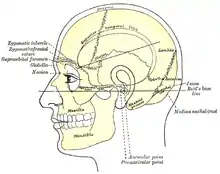

Side view of head, showing surface relations of bones. (Mastoid process labeled near center.) | |